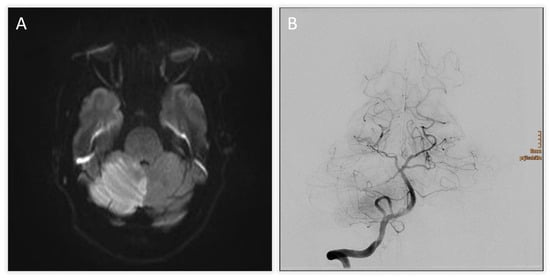

| +7 h | MRI follow-up | Brainstem infarction excluded; predominant cerebellar edema confirmed |

| +8 h | Neurosurgical intervention | Suboccipital decompression, ventricular drainage, and partial resection of necrotic tissue |